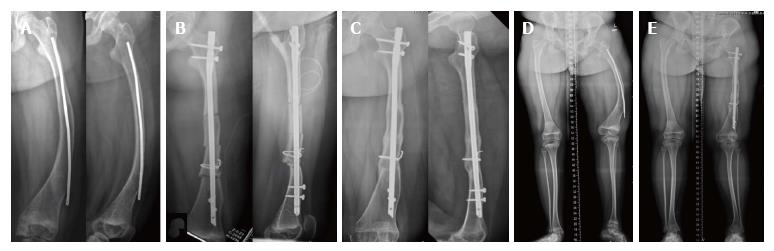

Using humeral nail for surgical reconstruction of femur in adolescents with osteogenesis imperfecta